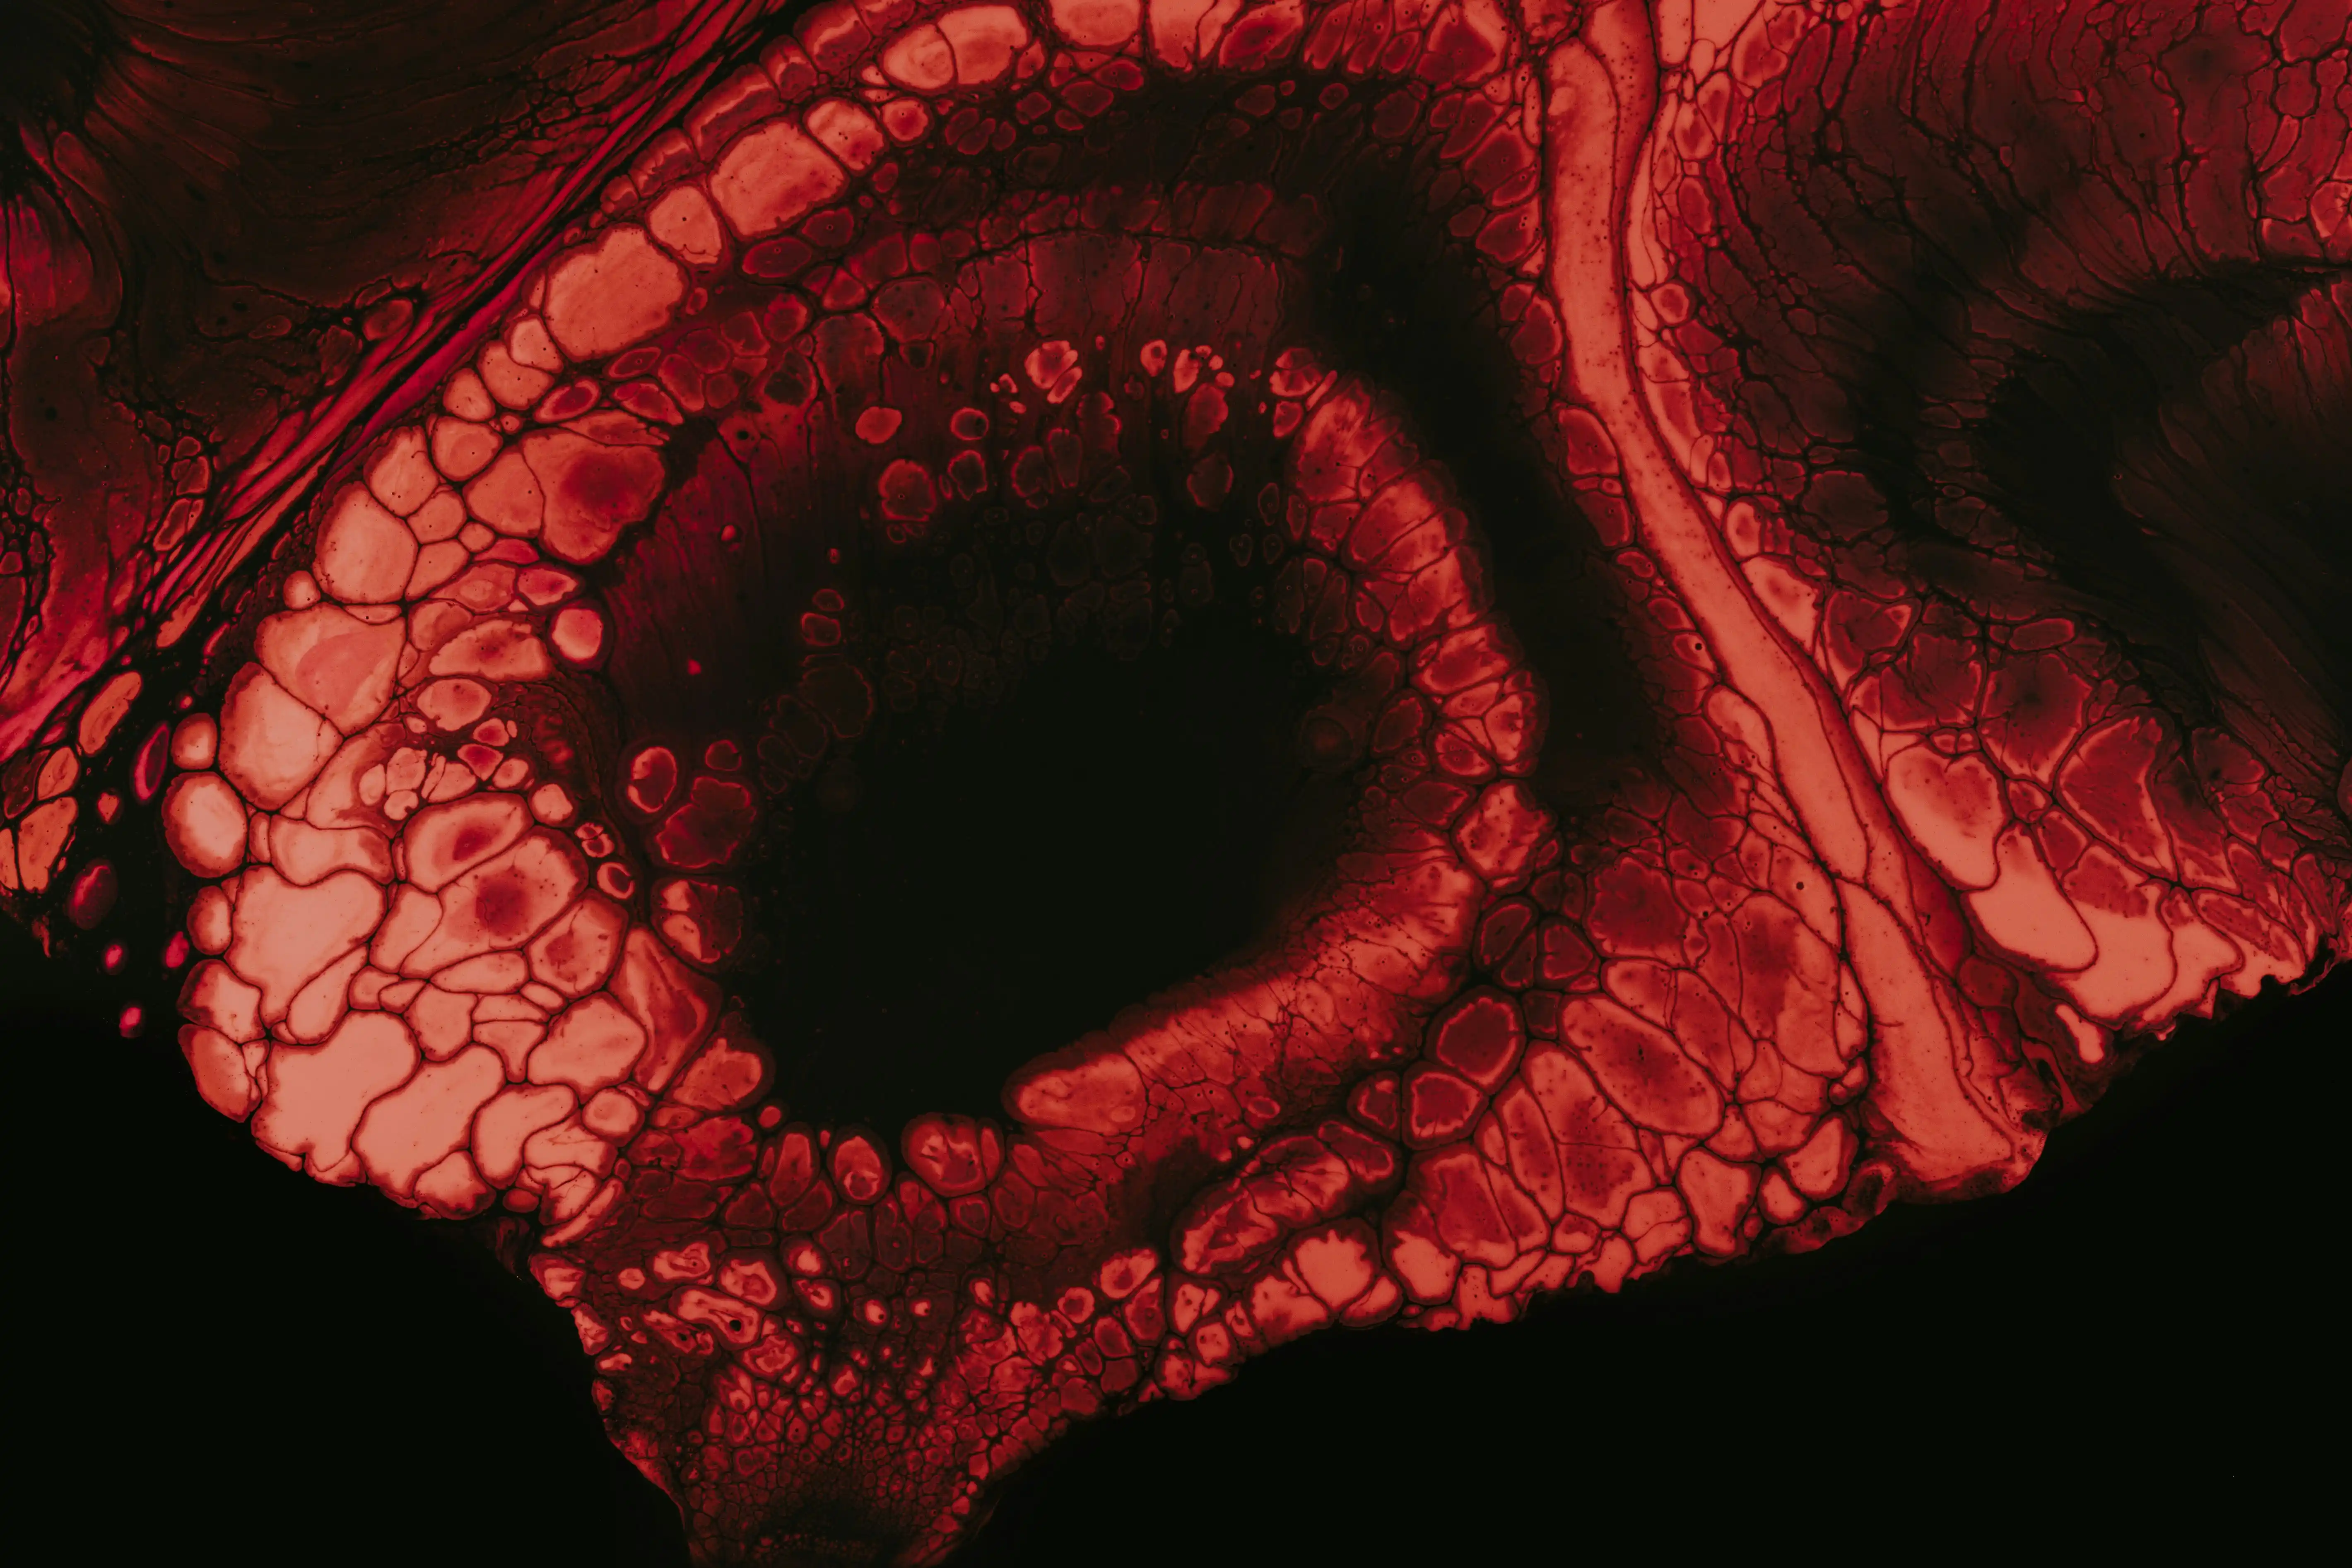

- 육안적 혈뇨: 신장, 방광, 요로의 염증이나 결석, 혹은 암이 원인일 수 있으며, 소변의 색이 붉거나 갈색으로 눈에 띕니다.

혈뇨 진단을 위한 첫 걸음은 바로 소변 검사입니다. 이는 가장 기본적이고 중요한 검진 방법으로, 혈뇨의 유무뿐 아니라 세균 감염 여부, 단백뇨 동반 여부 등 다양한 정보를 제공합니다.